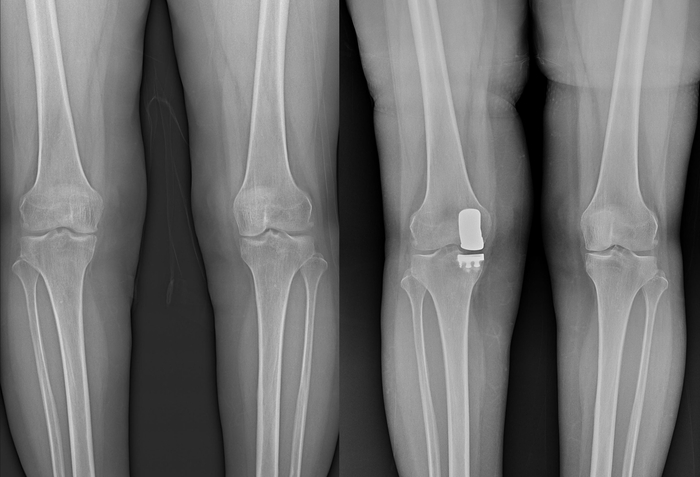

▲무릎 인공관절 수술 전-후 엑스레이 영상. 사진=연세사랑병원

무릎 인공관절 수술은 닳아버린 관절 표면을 제거하고 금속·고분자 재질의 인공관절로 대체해 통증을 줄이고 움직임을 회복하도록 돕는 수술이다. 보통은 무릎 안쪽·바깥쪽·앞쪽(슬개대퇴부) 등 전체 구역에 관절염이 퍼져 있을 때 무릎 전체를 교체하는 전치환술이 시행된다.

7일 보건복지부 지정 관절전문병원인 연세사랑병원에 따르면, 부분치환술은 무릎 관절 안쪽이나 바깥쪽 등 손상된 한 구역만 인공관절로 교체하고, 손상되지 않은 연골과 뼈, 인대는 그대로 보존하는 것이 특징이다. 환자의 원래 무릎 기능을 최대한 남길 수 있다는 점에서 의미가 있으며, 수술 범위가 전체치환술보다 작아 회복이 빠르다는 보고도 있다. 다만 이는 환자에 따라 차이가 있어 모든 경우에 동일한 결과가 나타난다고 단정할 수는 없다.